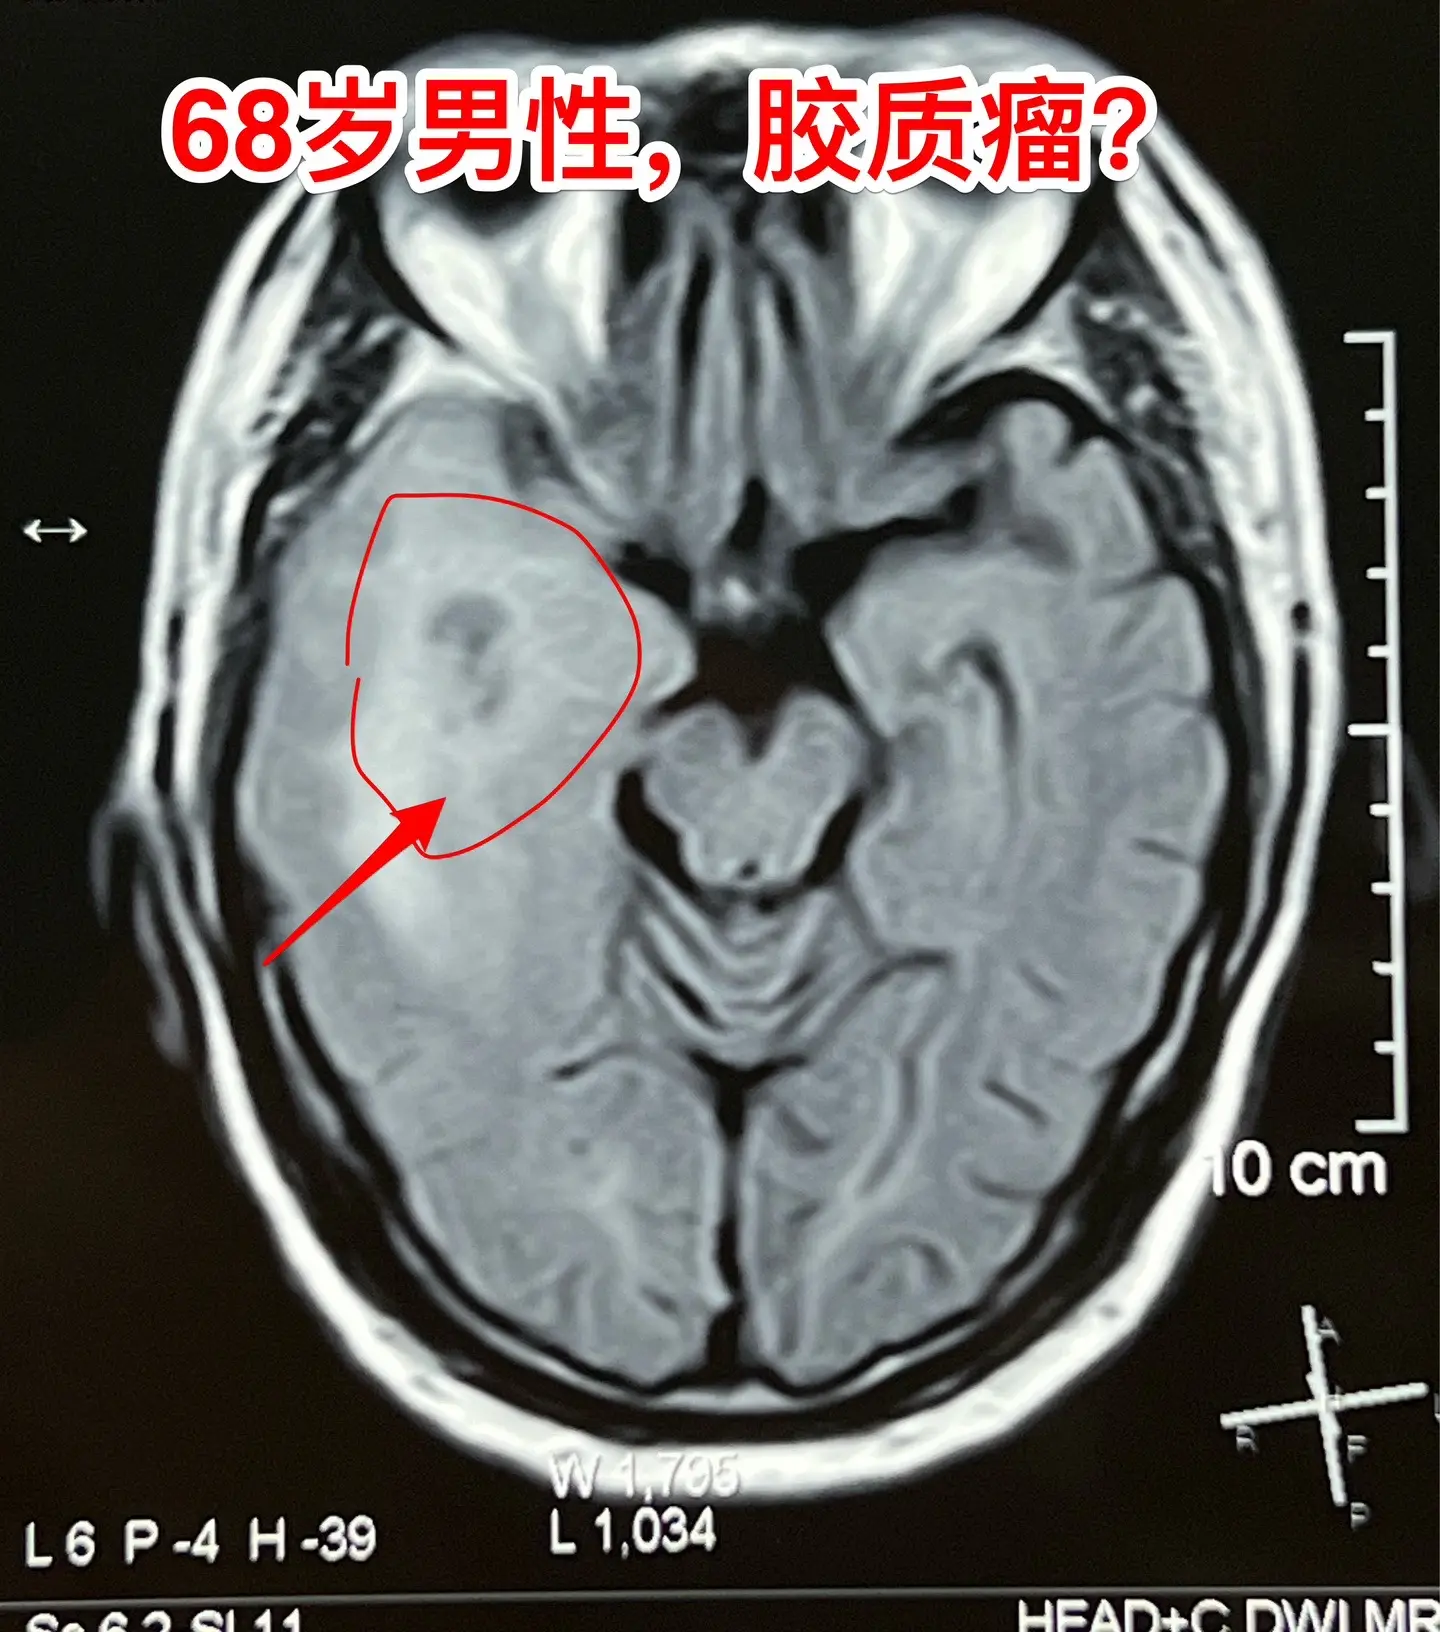

老人擀饺子皮的质量下降了,原因是什么?68岁的唐山市老人,擅长擀饺子皮、包饺子,平时擀出的饺子皮中央稍厚、四周均匀薄。然而近期他擀出的饺子皮形态不规整,厚薄一致,与平时的水准大相径庭,是什么原因呢?而且家人发现他穿鞋系鞋带动作又慢又笨拙!跟平时完全不一样。 病人的女儿在北京当医生。 到医院去检查脑部磁共振就发现脑部长了一个瘤。这个瘤位于左侧颞叶-基底节区,压迫内囊区域,虽然没有造成明显的偏瘫症状,但是也造成了左侧上下肢活动不灵活。 8.16到我这里来住院,8.23作了手术,术中的快速冰冻病理提示高级别神经上皮肿瘤,即胶质瘤的一种。 手术后老人没有出现明显的偏瘫症状。 这样的肿瘤单纯作手术是不够的,还需要作放疗、化疗。